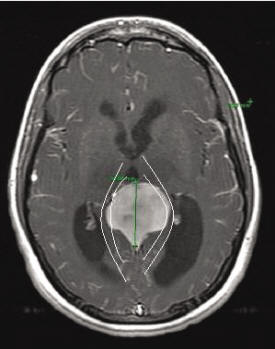

30+ Lining Of The Brain Tumor Images. Tissue swelling caused by the accumulation of fluid. Sometimes, cancer spreads from another part of the body into the brain resulting in a tumor types:

Primary tumors start in brain tissue, while secondary tumors spread to the brain from another area of the body. They are considered to be life threatening because they primary brain tumors may spread to other parts of the brain or to the spine, but rarely to other organs. Malignant brain tumors are generally more serious and often are life threatening.

They can come from the neurons, the glial cells, the lining of the brain, or from specific structures in the brain.

Brain tumors include numerous benign and malignant tumors in the brain. In other parts of the brain. Brain tumors occur when cells in the brain begin to grow out of control and start to displace or invade nearby tissues. People with a brain tumor may experience the following symptoms or signs.